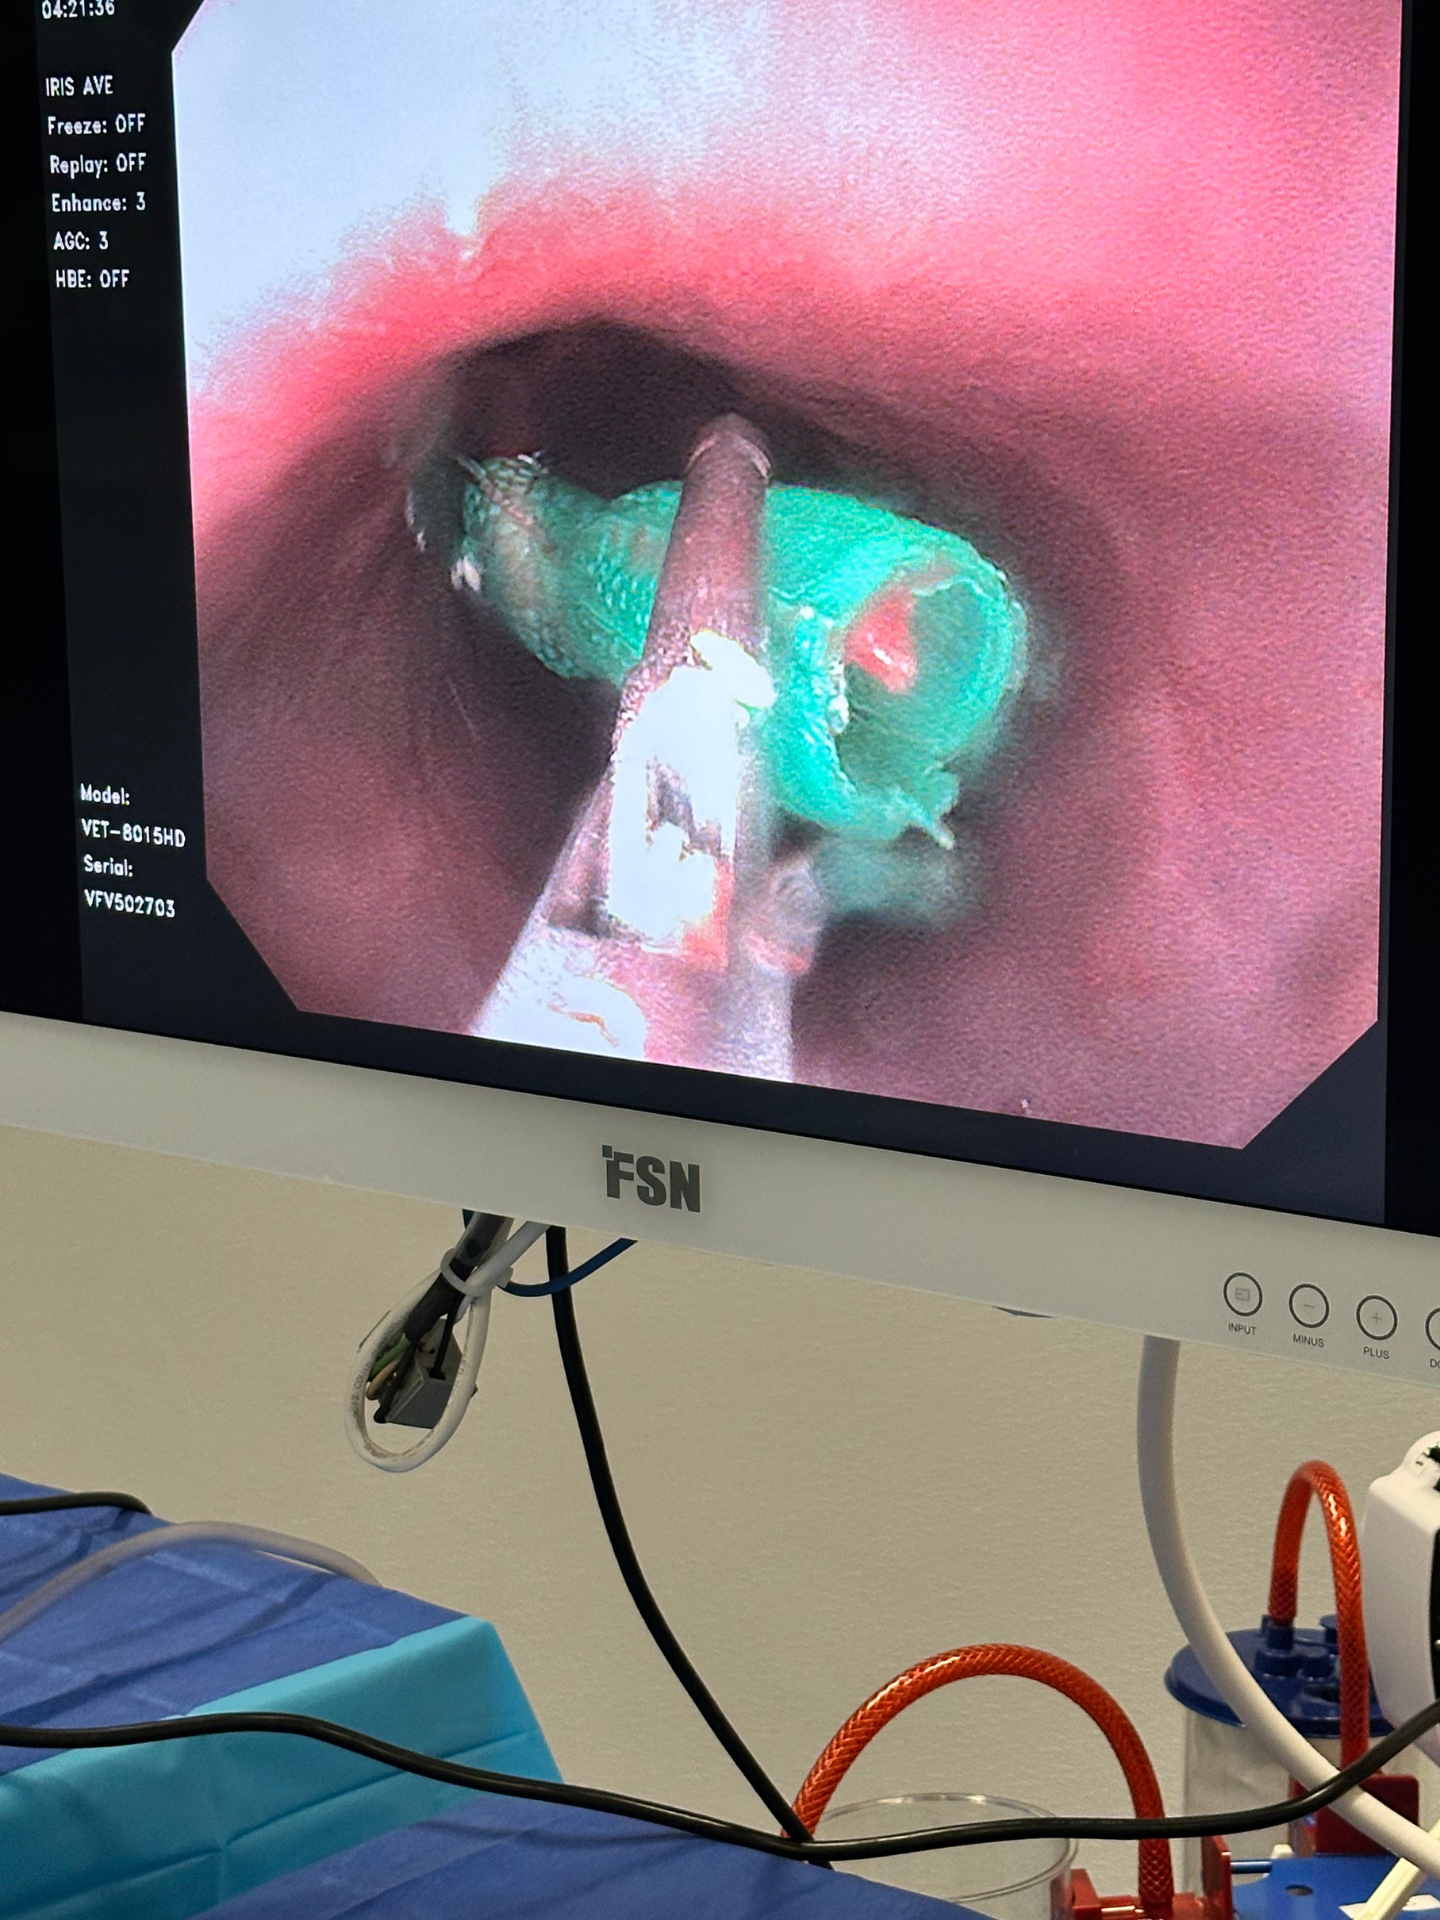

Pet endoscopy is a valuable diagnostic and treatment tool for pets with gastrointestinal issues. It is a minimally invasive procedure that allows veterinarians to examine the inside of your pet’s gastrointestinal tract using a small, flexible tube with a camera attached (endoscope). This procedure can help diagnose and treat a variety of gastrointestinal issues, including inflammation, foreign objects, tumors, and more. Our ER primarily specializes in foreign body removals and does not perform elective biopsy-only procedures.

In addition to diagnosing gastrointestinal issues, pet endoscopy can also be used to perform therapeutic procedures such as removing foreign objects, taking biopsies, and treating bleeding ulcers, all while minimizing trauma to surrounding tissues.